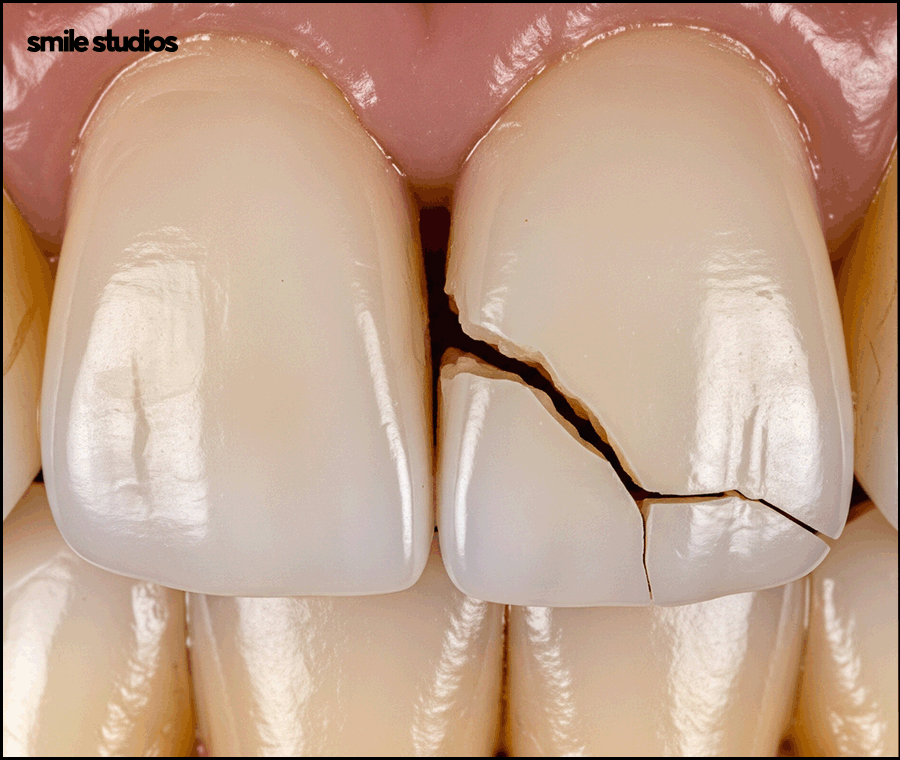

아직은 미세한 수준이라고 하더라도 지속적으로 사용하게 되면서 균열이 더 깊어질 수 있는데요.

내부 깊숙한 곳까지 금이 이어지면서 심한 통증을 유발하거나 파절까지 발생하기도 합니다.

자칫 뿌리 부근까지 금이 이어져 부러질 경우 발치를 해야 할 수 있습니다.